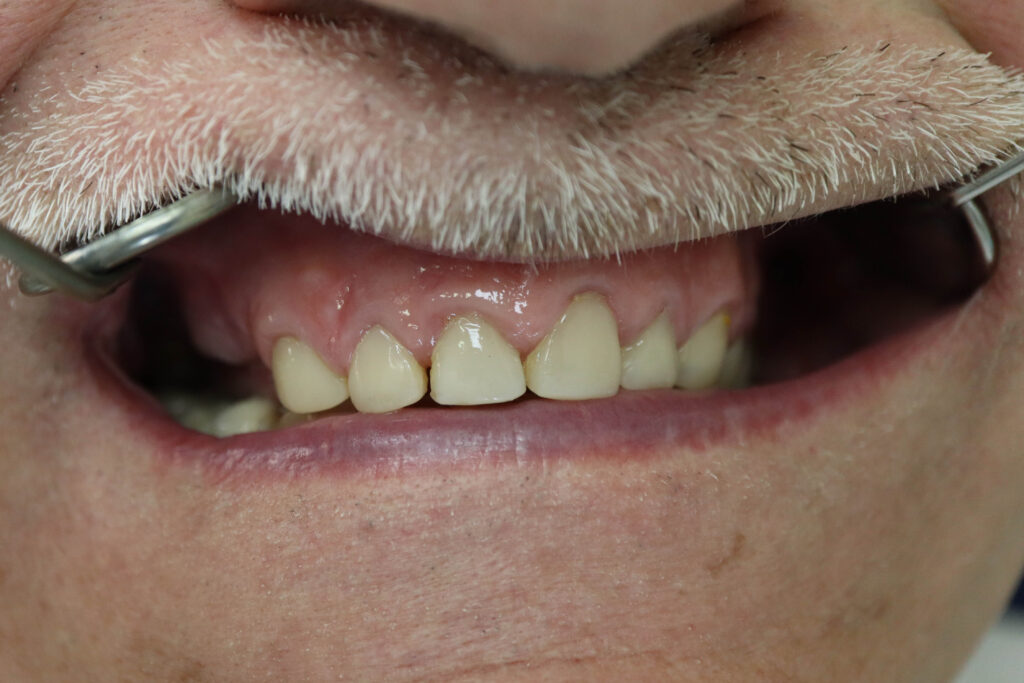

Ситуация до лечения

пациент до имплантации